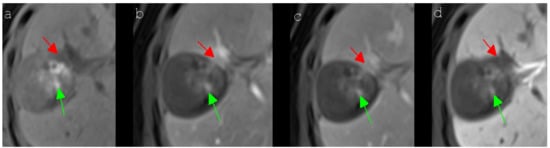

Figure 4. A 64-year-old woman with a local tumor progression in the peripheral ablation zone (segment V/VIII) six months after IRE of an HCC, which presented a typical signal behavior in Gd-EOB-DTPA-based MR imaging. The HCC showed a hypointense signal (red arrow) in the unenhanced T1 MR image (a), an obvious hyperintense signal (red arrow) in the contrast-enhanced T1 arterial phase MR image (b), a slight wash-out (red arrow) in the contrast-enhanced T1 portal venous phase MR image (c) and a hypointense signal (red arrow) in the contrast-enhanced T1 delayed phase MR image (d). In addition to this, the central part of the ablation area showed several hyperintense spots (green arrow), which could be detected in all presented MRI sequences (ad), being caused by post-interventional bleeding.